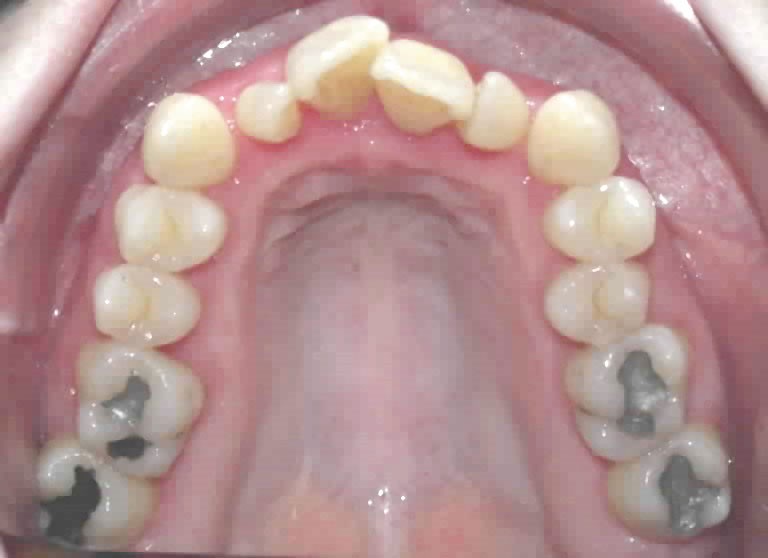

• endoalvéolie maxillaire avec occlusion inversée antérieure et bilatérale,

• fortes malpositions des incisives supérieures (dont 22 qui est en rotation axiale disto-palatine de 90°), • dysharmonie dento-dentaire (12 en « grain de riz » est aussi en rotation marginale disto-palatine de 45°),

• anomalie de la forme d’arcade maxillaire, 47, 18 et 28 sont absentes. (fig. 1 à 8), 48 est positionnée très postérieurement, quasiment au niveau de la branche montante (fig. 9 et 11).